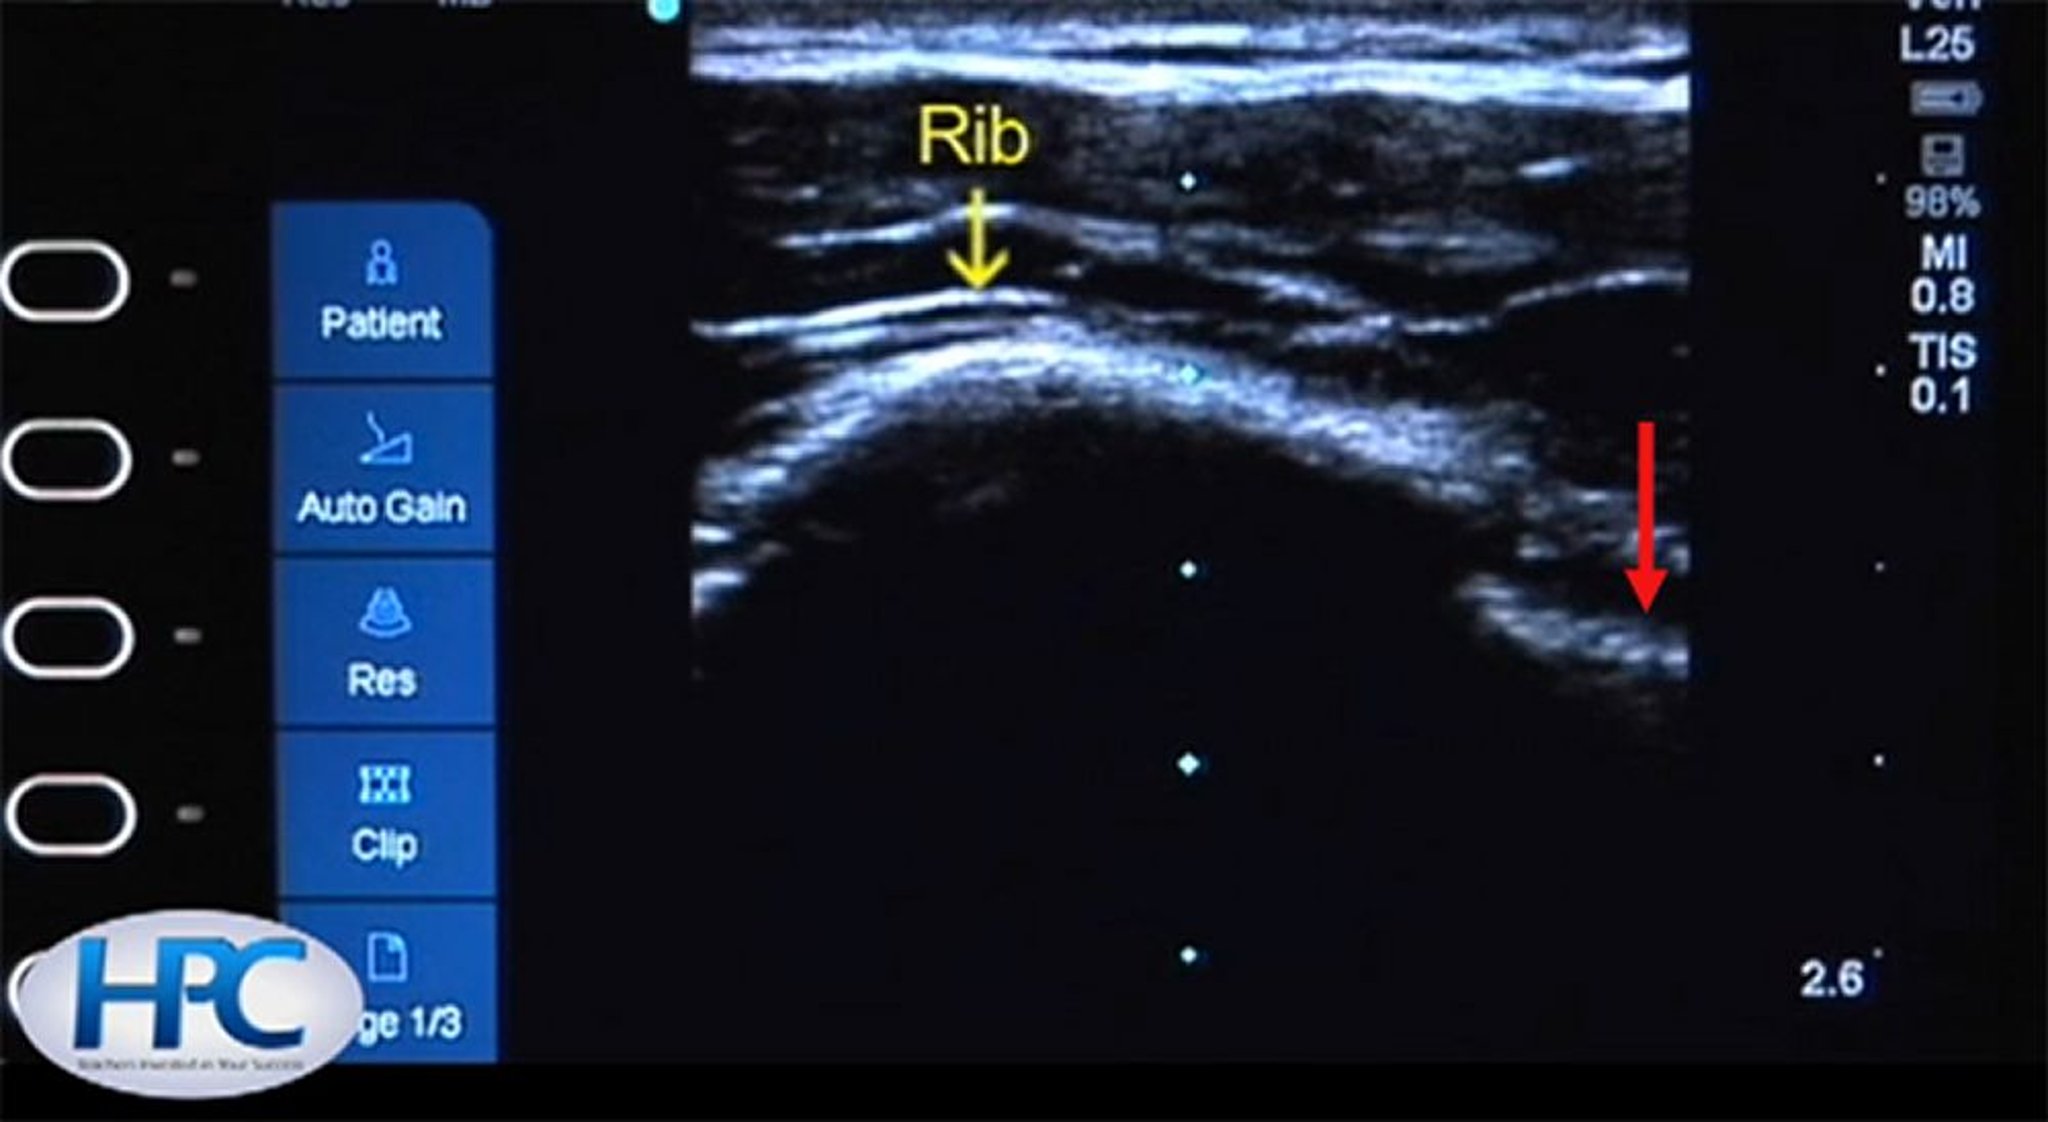

Aspect échographique des côtes et de la ligne pleurale

La côte (flèche jaune) apparaît comme une structure hyperéchogène (blanche) avec des ombres sous la côte. La ligne pleurale (flèche rouge) est visible dans l'espace intercostal.